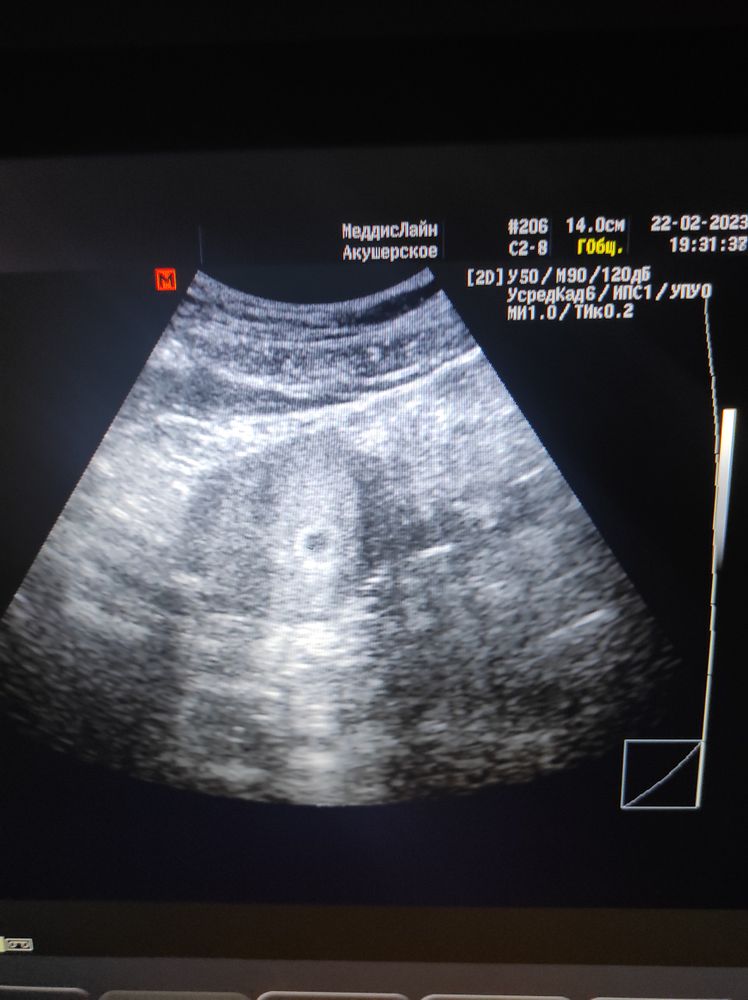

22.02 сходила на УЗИ. ПЯ в матке 7 мм. Срок на неделю меньше по УЗИ, чем по последним месячным.

Вот думаю 6-7 марта сходить на УЗИ, проверить наличие эмбриона и сердцебиения. Так как 22.02 увидели только плодное яйцо.

Сейчас по месячным у меня 7 недель и 3 дня, но если считать по УЗИ первому, то 6 недель и 2 дня.